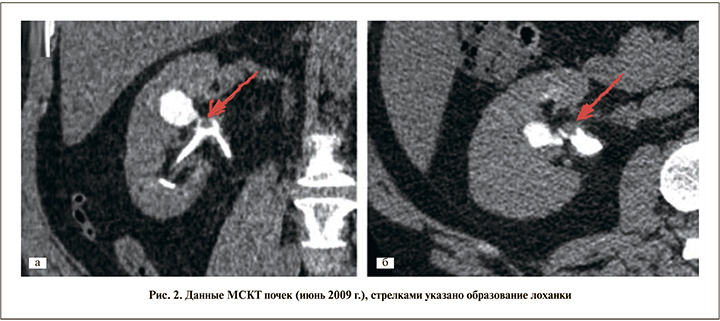

По данным МСКТ от 03.06.2009: по сравнению с исследованием от 24.03.2009 в лоханке правой почки сохранен дополнительный объем мягкотканной плотности (отчетливо выявлен в выделительную фазу в виде «полиповидного» дефекта наполнения): размер его уменьшился до 8×8,5 мм.

Там же определен кальцинат до 4,3 мм и отмечено расширение прилежащей средней чашечки до 18 мм. В артериальную фазу плотность патологической зоны увеличилась с 25 до 45 HU. Признаков распространения опухолевого процесса не выявлено (рис. 2). В лабораторных анализах – незначительная эритроцитурия и протеинурия.